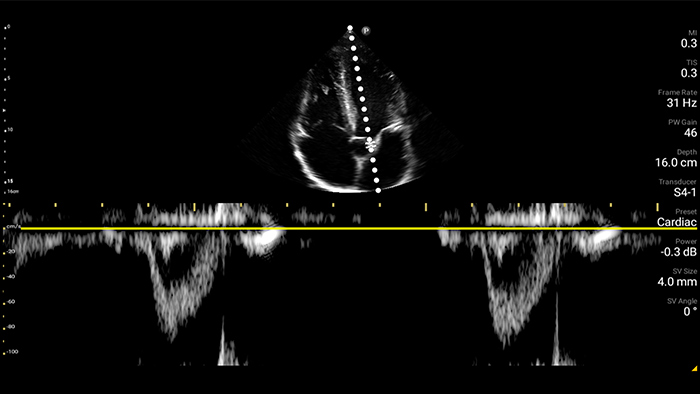

Congestief hartfalen is een groeiend probleem. Door echografie op uw praktijk te bieden, kan deze aandoening vroegtijdig worden ontdekt en de overlevingskansen aanzienlijk worden verbeterd.

Harttamponade vermomt zich als buikpijn

Beoordeling van de functie van het linkerventrikel